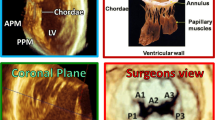

In most situations, 2D TTE can adequately assess the etiology and quantify the severity of MR. 2D TEE (Fig. 1a) is preferred when TTE is suboptimal or technically limited, or when complex, calcified or endocarditic lesions are being evaluated.

Fig. 1 Example of primary mitral regurgitation (MR) (a–d): Prolapse of the middle posterior mitral valve scallop (P2) shown in a long-axis view of (a) a two-dimensional (2D) transesophageal echocardiogram (TEE) with associated severe, eccentric, anteriorly directed MR [red arrows indicate the vena contracta (VC), yellow arrow indicates the proximal isovolumic surface area (PISA)] and (b) a three-dimensional (3D) TEE en face or surgical view. Echocardiographic multiplanar reconstruction of the VC area and cardiac magnetic resonance (CMR) steady-state free processing (SSFP) short-axis view of regurgitant orifice area are shown in panels c and d, respectively. Example of secondary MR (e–h): Leaflet tenting with significant MR is shown in a long-axis view of a (e) 2D TEE and en face view of a 3D TEE (f). Echocardiographic multiplanar reconstruction of the VC area (g) and CMR SSFP image of the regurgitant orifice (h) show the crescent shape of the orifice in secondary MR. Panels g and h were adapted from reference [38]. AO aorta, LA left atrium, LV left ventricle.

The 2D echocardiographic methods described above are complemented and enhanced by 3D echocardiography. 3D TTE-guided direct planimetry of the VC cross-sectional area, measurements using the PISA method, and volumetric assessment of EROA have all been compared to 2D echocardiography and shown to be accurate regardless of MR etiology or orifice shape [29–31]. In patients with MVP, 3D TTE provides reliable data regarding anatomic localization of prolapsing scallops with accuracy comparable to that provided by 2D TEE and overall allows better spatial localization of commissures and valvular pathology [32].

3D TEE provides a distinct advantage over 2D TEE because of its ability to visualize the entire MV apparatus with more detail. It has been shown to be superior to 2D TEE for accurate localization of pathology, including scallop-specific involvement based on Carpentier’s classification in three anterior segments (lateral A1, middle A2, medial A3) and three posterior segments (lateral P1, middle P2, medial P3) (Fig. 1b). Similarly to 3D TTE, quantification of MR severity is also improved using 3D TEE, which allows direct visualization and planimetry of the VC cross-sectional area by using multiplanar reconstruction software (Fig. 1c, g). This alternate measure of EROA is not affected by orifice shape or jet direction; this may be of particular importance in secondary MR, in which the crescentic regurgitant orifice might otherwise be underestimated by using linear VC (Fig. 1e, g) [33]. Assessment by 3D TEE has been shown to be both feasible and accurate as compared with CMR and may reclassify a significant proportion of patients to a greater MR severity when compared with 2D TEE results [34].

Though data are limited, several studies have indicated that CMR may be useful for establishing MV morphology and pathology. Comparison of CMR with TTE has shown that standard TTE diagnostic criteria for MVP, specifically systolic MV leaflet excursion into the LA of at least 2 mm, may be applied to CMR with high sensitivity and specificity [35]. In the same study, MVP patients with papillary muscle fibrosis by late gadolinium enhancement (LGE) were at higher risk of ventricular arrhythmia on Holter monitoring. In another study of patients with acute myocardial infarction, CMR identified useful correlations between LGE-based infarct distribution and papillary muscle involvement and severity of secondary MR [36•]. Planimetry of the anatomic regurgitant orifice area (AROA) using CMR has been validated against both invasive methods and calculation of EROA using the PISA method with TTE [37]. Assessment of AROA has also confirmed the asymmetric and crescentic shape of the regurgitant orifice in secondary MR, suggesting that it may be possible to distinguish etiologies of MR using parameters of MV geometric anatomy (Fig. 1d, h) [38].